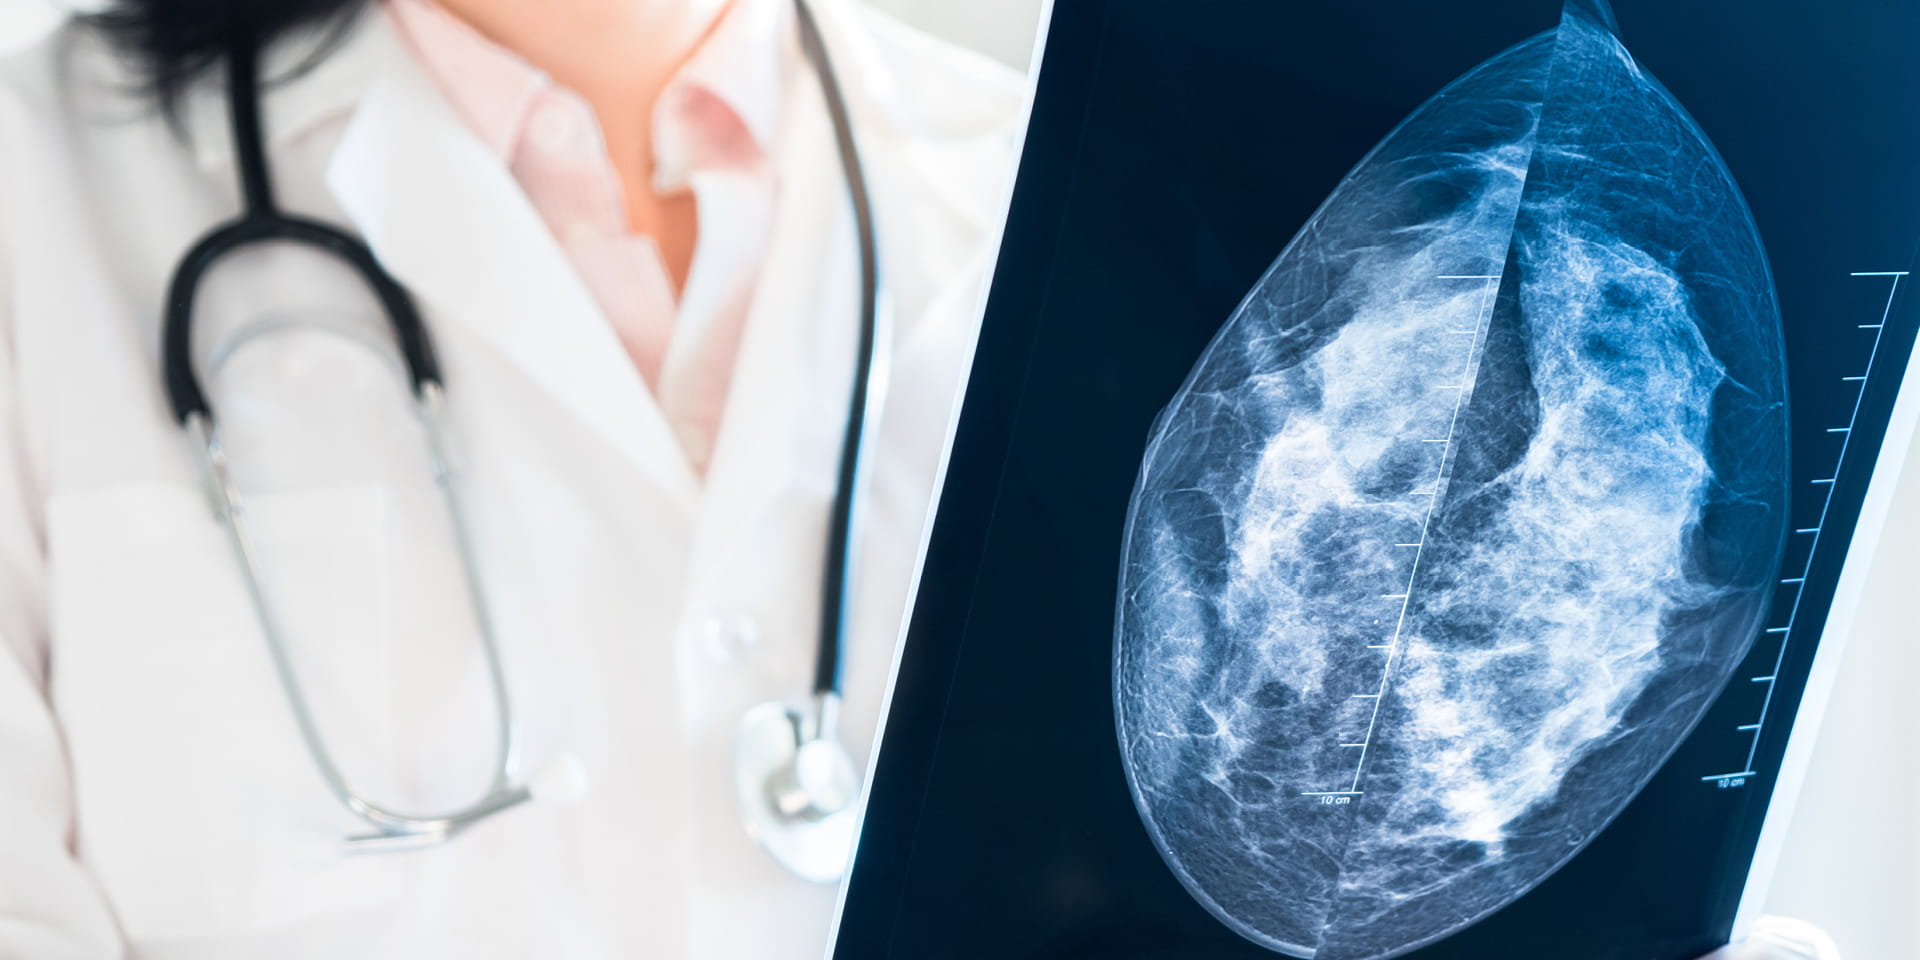

Doctor holding mammography film

Doylestown Health offers an advanced technology that gives physicians unprecedented views of the breast and may aid in the early detection of breast cancer, particularly for patients with dense breasts. This imaging service is called 3D mammography or breast tomosynthesis.

Unlike digital mammography, which produces a 2-dimensional image of the breast, 3D mammography creates a series of images that allows the radiologist to view the breast in multiple, connected slices. This process is similar to how a computed tomography (CT) scanner produces images of various structures inside the body.